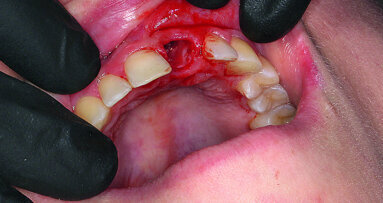

An oral examination revealed a localised swelling in the #11 region with a discharging sinus (Fig. 2). The abutment teeth #12 and 21 were not tender to percussion. A radiographic examination revealed a well circumscribed radiolucency with a well-defined border in the region of #11 measuring 1 cm by 0.5 cm. The radiolucency was mesial to the root of #12. A small radiopaque mass was observed within the radiolucency. Tooth #12 had an adequate endodontic filling with small periapical radiolucency (Fig. 3).

A semi-lunar incision was made in the region of #11 apical to the discharging sinus. The cytic lesion was removed and the defect was curetted and grafted with xenograft (Bio-Oss, Geistlich Pharma AG). Primary closure was performed to encourage better healing. Post-operative healing was uneventful. The biopsy revealed a radicular cyst and the presence of a root remnant, possibly part of #11.

Figs. 1–4: Pre-treatment lower facial view (Fig. 1). Poor aesthetic of the existing fixed partial denture (Fig. 2). Pre-treatment panoramic radiograph. Note the radiolucency over the maxillary right central incisor (Fig. 3). Placement of Replace Select tapered implant (Fig. 4).

After a healing period of two months, the fixed partial denture was removed and a provisional fixed partial denture with an ovate pontic design was fabricated (Pro-Temp Garant Temporization Material, 3M ESPE). A Replace Select tapered implant 4.3 mm x 13 mm (Nobel Biocare AB) was placed in the location of #11 (Figs. 4&5). Additionally, xenograft (Bio-Oss, Geistlich Pharma AG) was added to the buccal surface of the edentulous ridge to augment the bony deficiency. Primary closure was achieved with Vicryl resorbable suture and the provisional fixed partial denture was cemented in provisional cement (RelyX Temp NE Temporary Cement, 3M ESPE). Endodontic treatment of #21 was performed during the implant healing period.